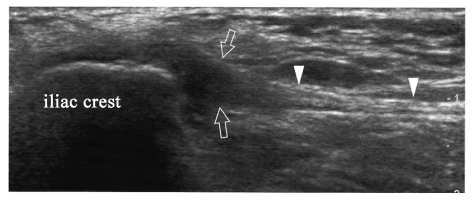

一 阔筋膜附着点肌腱病,患者右侧髂嵴疼痛和局部触痛

阔筋膜张肌在髂嵴(iliaccrest)附着点水平12~5MHz超声冠状断面显示阔筋膜附着点周围部分肿胀回声减低,说明局部肌腱病(箭头)。观察远端部分(箭头端)正常增厚和高回声表现